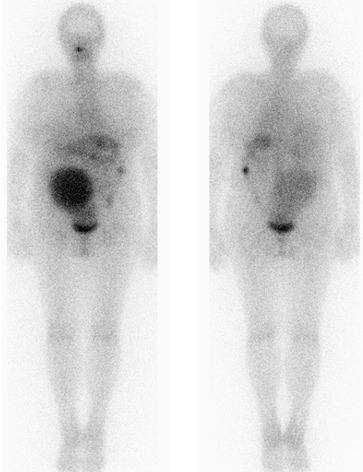

Celotělová scintigrafie po terapii 131I 7,4 GBq: patologická akumulace

131I v obrovském oválném útvaru v pravé polovině břišní dutiny. Nevelká depozice radiojodu ve střevech, vyloučený radiojod v močovém měchýři.

(obr.1 – celotělová scintigrafie za 5 dnů po terapii), (obr.2 – celotělová scintigrafie za 6 dní po terapii).

/ Obr. č. 1: Celotělová scintigrafie 5 dnů po podání 7,4 GBq 131I - přední a zadní projekce /

/ Obr. č. 2: Celotělová scintigrafie 6 dní po podání 7,4 GBq 131I - přední a zadní projekce /